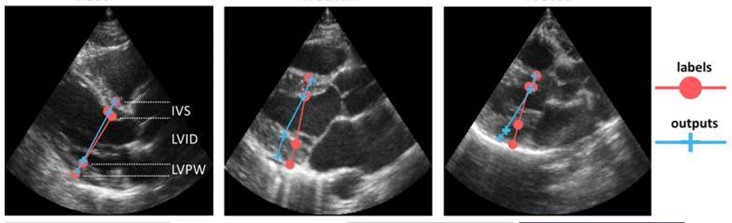

Through the INCUS project (2016-2019), NR and GE Vingmed successfully automated tasks for detecting the heart’s view angle, selecting appropriate Doppler measurements, and measuring distances within images. Several of our solutions have been integrated into Vingmed ultrasound scanners and are now in clinical use.

Gilbert, A., Holden, M., Eikvil, L., Aase, S. A., Samset, E., & McLeod, K. (2019). Automated left ventricle dimension measurement in 2D cardiac ultrasound via an anatomically meaningful CNN approach. I Q. Wang, A. Gomez, J Hutter, K. McLeod, V. Zimmer, O. Zettinig, R. Licandro, E. Robinson, D. Christiaens, E. Abaci Turk & A. Melbourne (Eds.), Smart Ultrasound Imaging and Perinatal, Preterm and Paediatric Image Analysis (1st ed., pp. 29-37). Springer. DOI: 10.1007/978-3-030-32875-7.